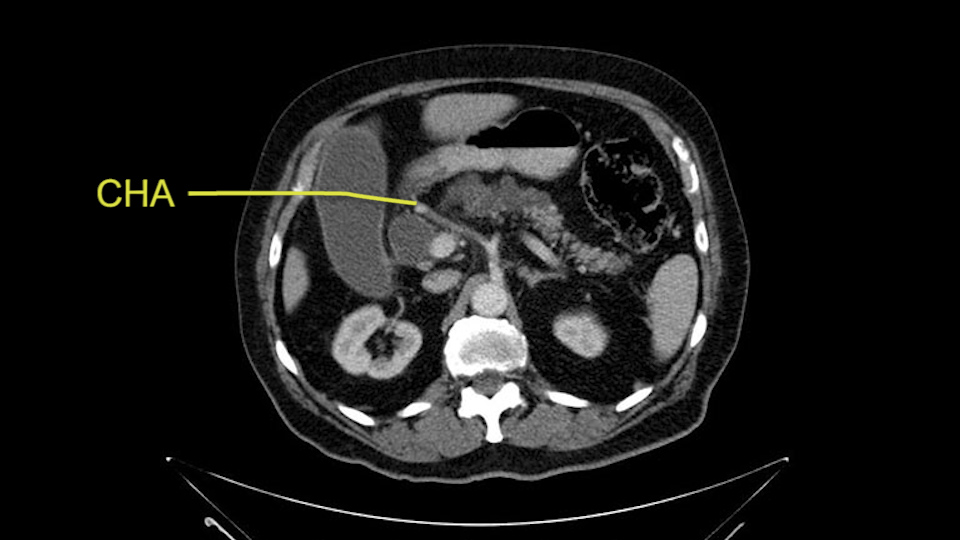

He has no liver metastases or obvious metastatic disease. On reviewing his CT scan, he has normal vascular anatomy; he has no involvement of the portal vein by the looks of it, or the superior mesenteric vein.

He has normal arterial anatomy: no accessory or replaced right hepatic artery, which is important because sometimes the right hepatic artery can come behind the neck of the pancreas and you have to be careful of that in a Whipple dissection.

Then you look for anomalies. The one you worry about the most doing a Whipple is a replaced or aberrant right hepatic artery coming off the SMA at its origin. So again, find the SMA. You can find it because the renal vein goes through it. Follow it up, up-up-up. Nothing coming off of there that I can see here. Nothing coming off of it, nothing coming off of it and just to confirm it, look at the celiac trfurcation. There’s the celiac, there’s the bifurcation, there's the splenic artery, hepatic artery. Make sure there’s a right, which there is here. The right usually goes under the bile duct: important when you’re going around the bile duct to do a Whipple. A replaced right goes under the portal vein and the bile duct way over here on the right. That’s about it.